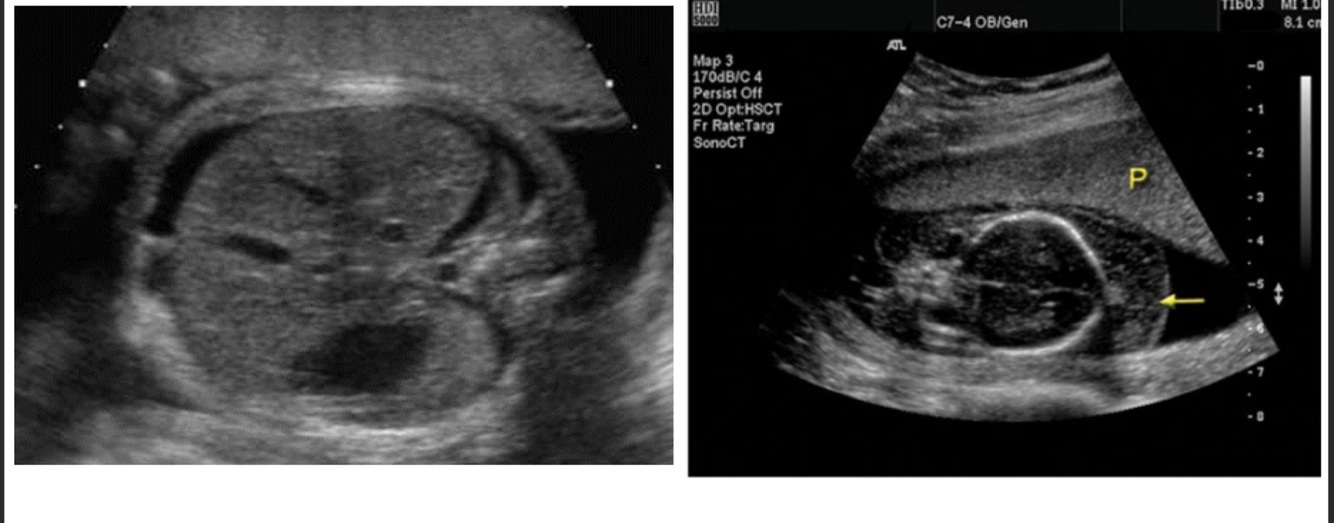

What does this image demonstrate?

Ground glass appearance